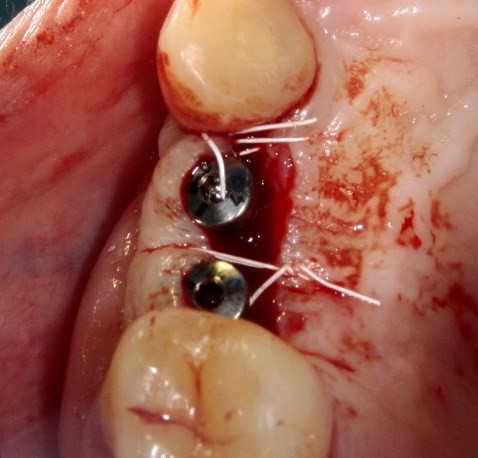

Опыт применения коллагеновой матрицы Mucograft в клинической практике.